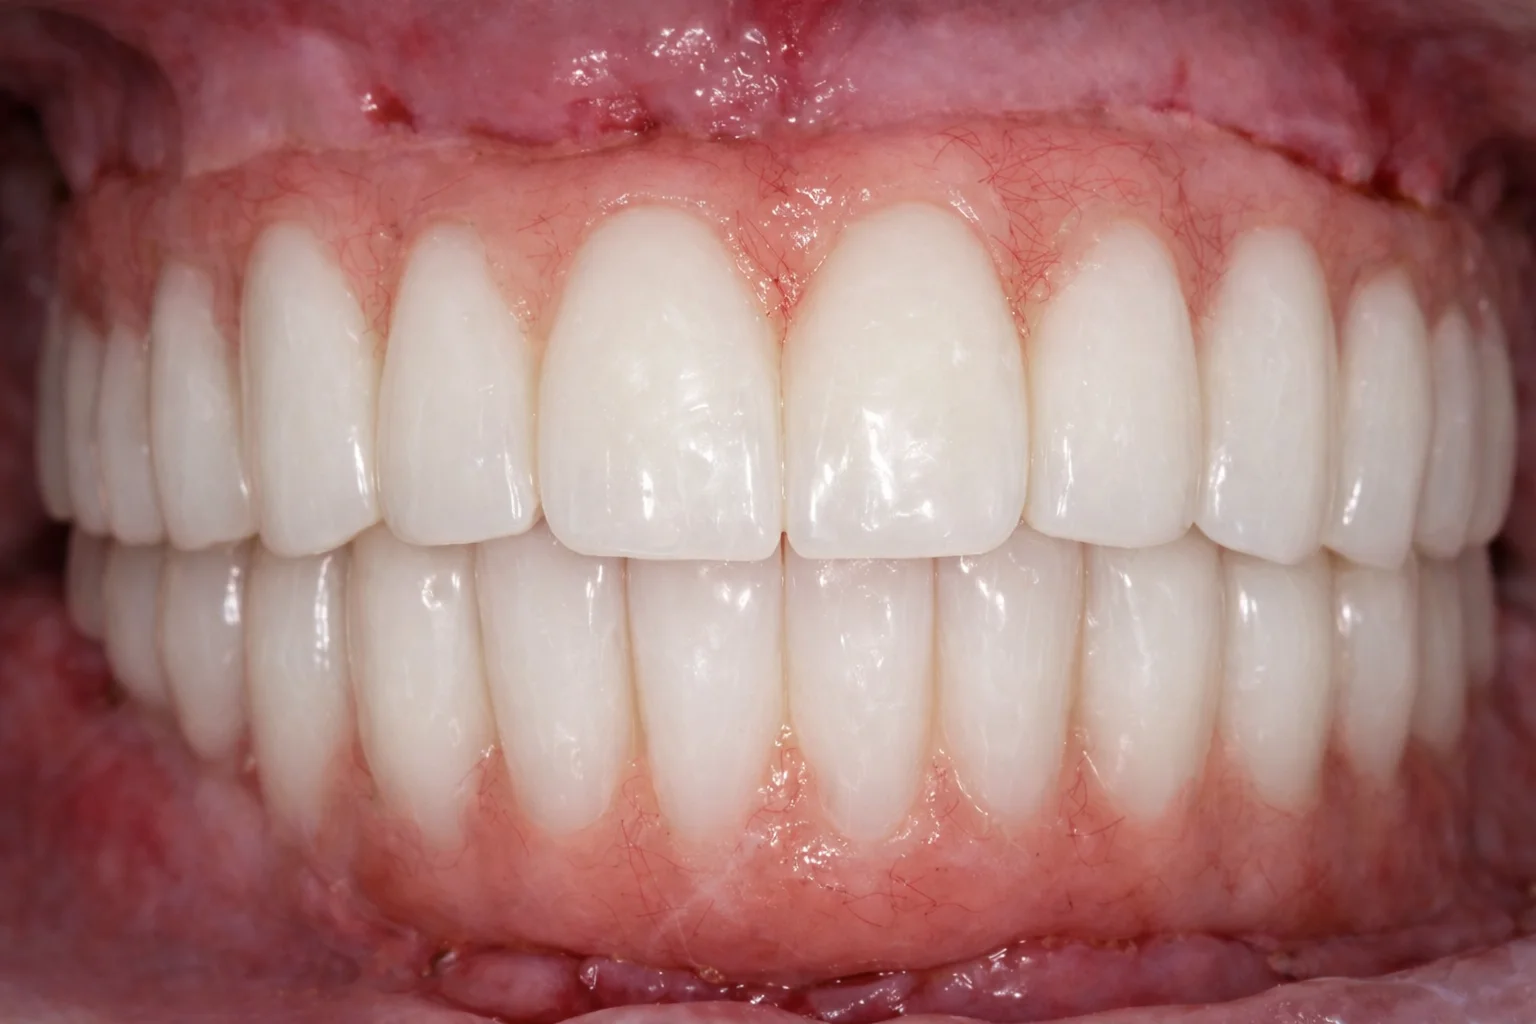

«Говорили, что это невозможно». Пациентка долго слышала, что в её ситуации полноценное восстановление зубов невозможно или потребует множества этапов и длительного лечения. Это останавливало её от решения проблемы на протяжении многих лет. Частичное отсутствие зубов на верхней и нижней челюсти требовало функционального и предсказуемого решения.

На консультации мы провели подробную диагностику и нашли варианты лечения. В итоге была выполнена тотальная реабилитация. В день операции установлены имплантаты и несъёмные конструкции.

Уже через 4 часа была восстановлена жевательная функция и anti-age-эффект за счёт правильной опоры мягких тканей.